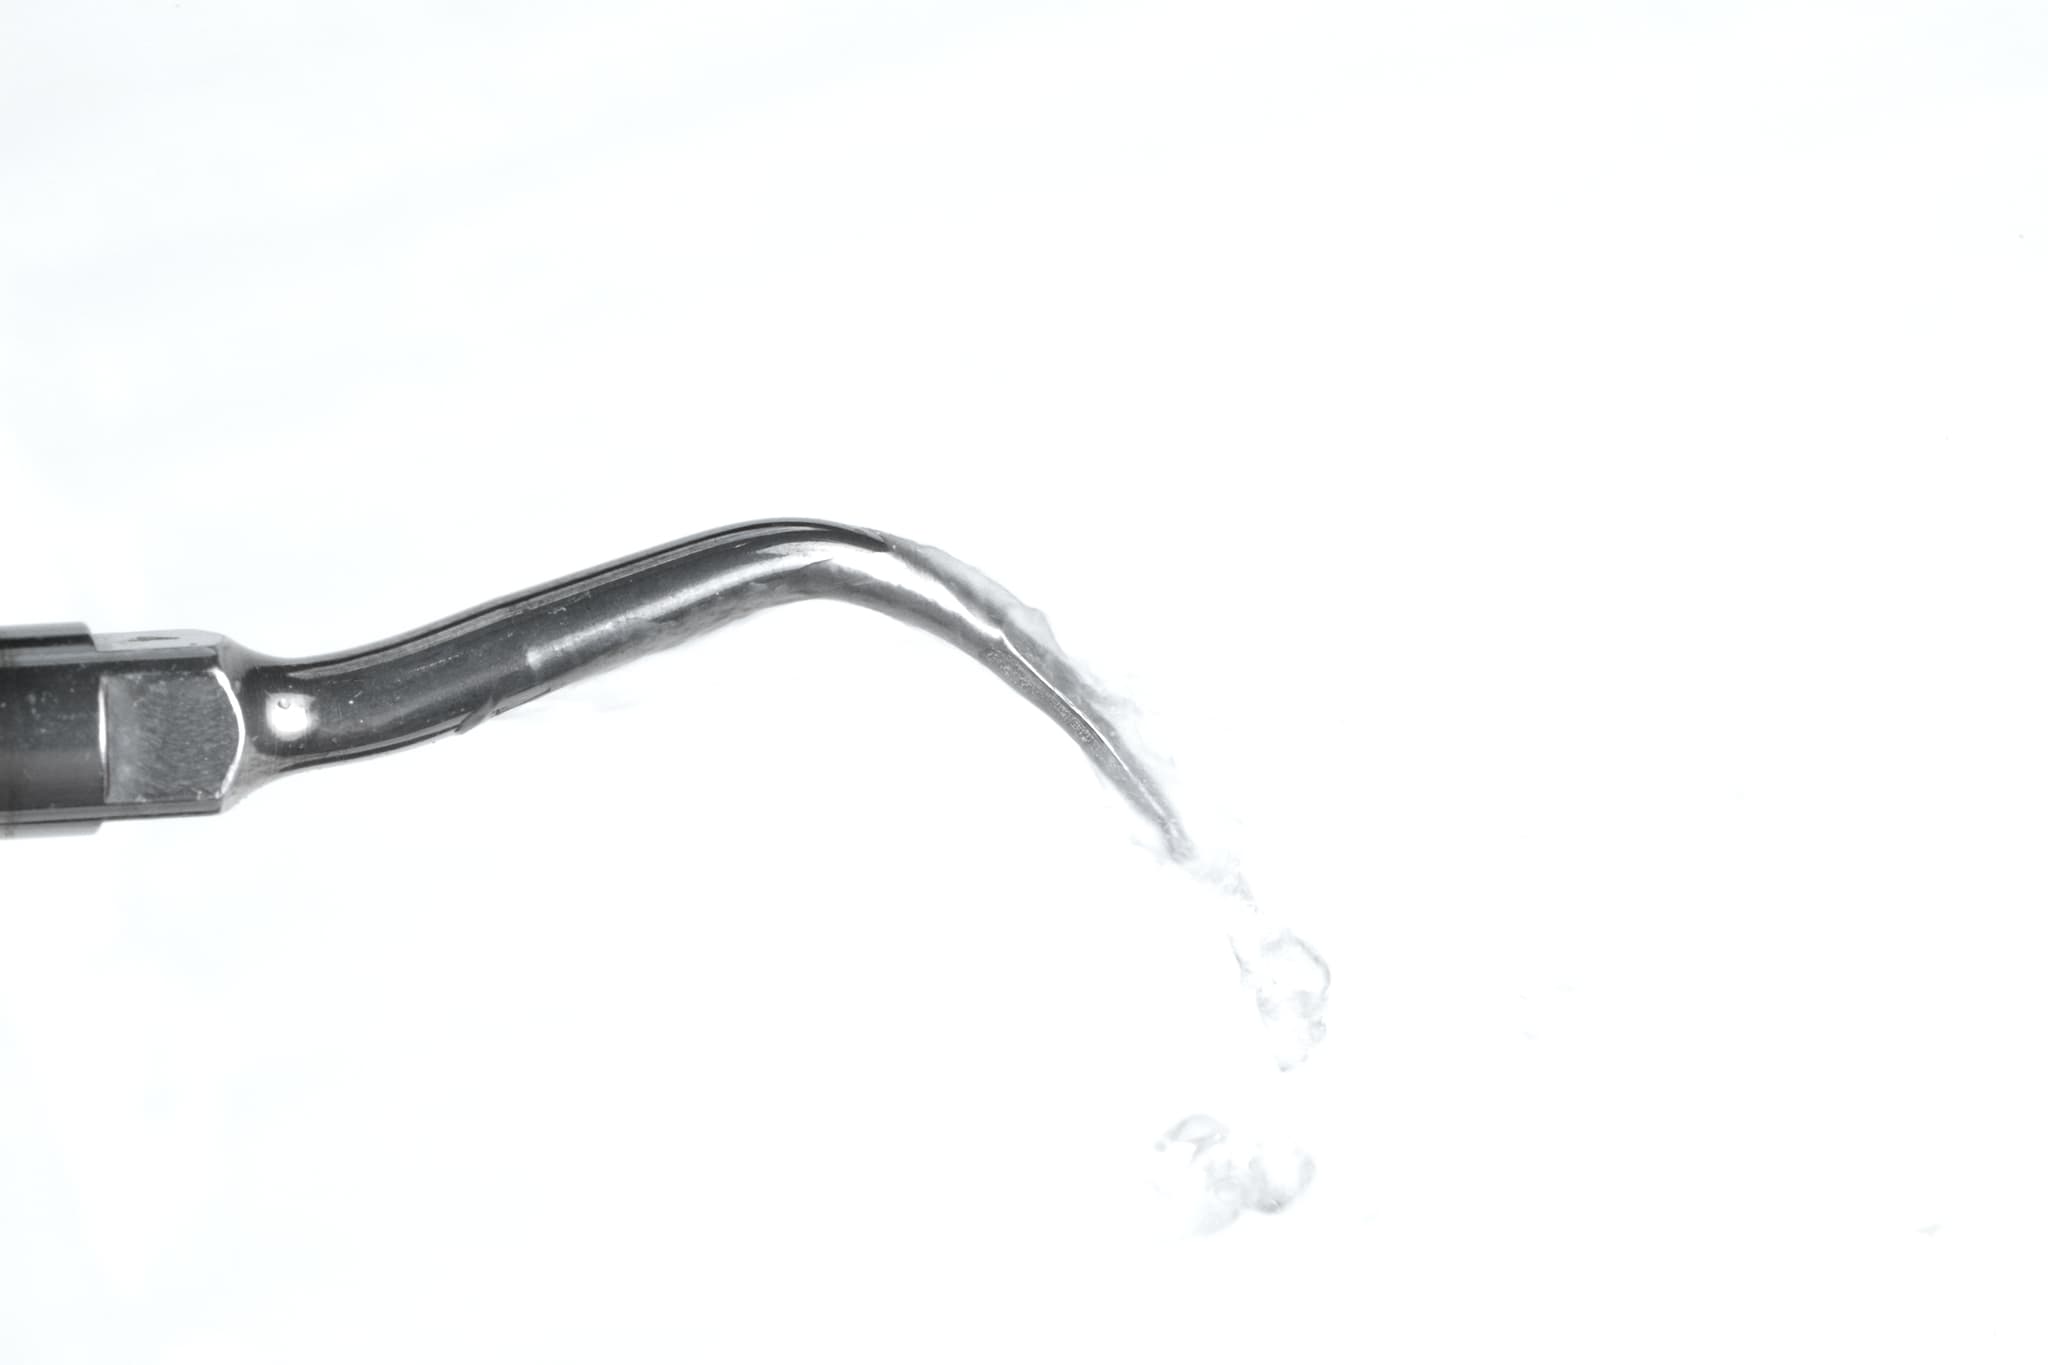

În funcție de severitate, tratamentul poate include detartraj subgingival și planare radiculară, terapie asistată cu laser sau tratamente antimicrobiene țintite. Intervenim fără lambou ori de câte ori este posibil, concentrându-ne pe curățarea suprafeței radiculare și oprirea progresiei—fără traumă inutilă.

Majoritatea tratamentelor sunt minim invazive și bine tolerate sub anestezie locală. Curățările asistate laser sau cu ultrasunete cresc confortul și sprijină vindecarea.